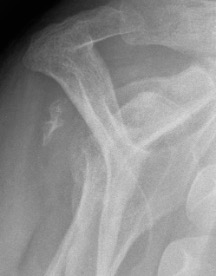

Xray

Signs of chronic shoulder dislocation

Chronic shoulder dislocation with large Hill Sachs and minimal glenoid deficiency

Chronic shoulder dislocation with large Hill Sachs and significant glenoid deficiency